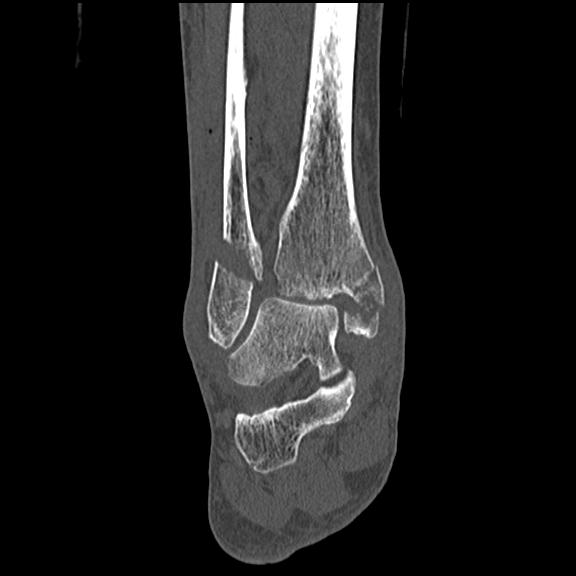

102755 1/4 2R 1/15 2R 右足関節 68歳女性 右三果脱臼骨折